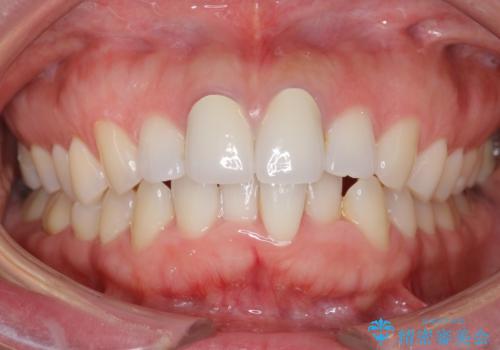

終了時

治療について